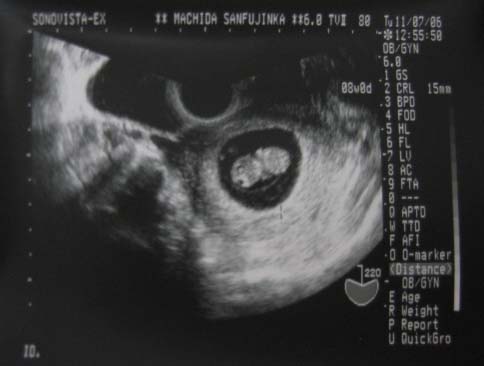

今回はこんなかんじでした。

タマゴが二つ並んでるみたい。。。やっぱり一週間ではあんまり変化は見られませんねぇ(笑)